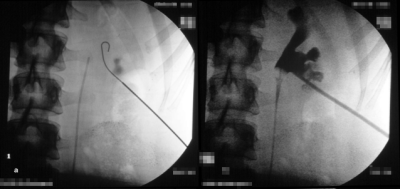

Bei der perkutanen Litholapaxie wird ausgehend von einer zumeist sonographiegesteuerten Punktion des Nierenhohlraumsystems und Dilatation des Punktionskanals ein Pyeloskop zur Steinzertrümmerung bzw. Entfernung eingeführt (Abbildung 7).

Bei der Anwendung perkutaner Methoden im Kindesalter ist die Größe des Instruments von Bedeutung. Hier hat sich ein miniaturisiertes Pyeloskop bewährt:

Mini-PERC der Firma Wolf